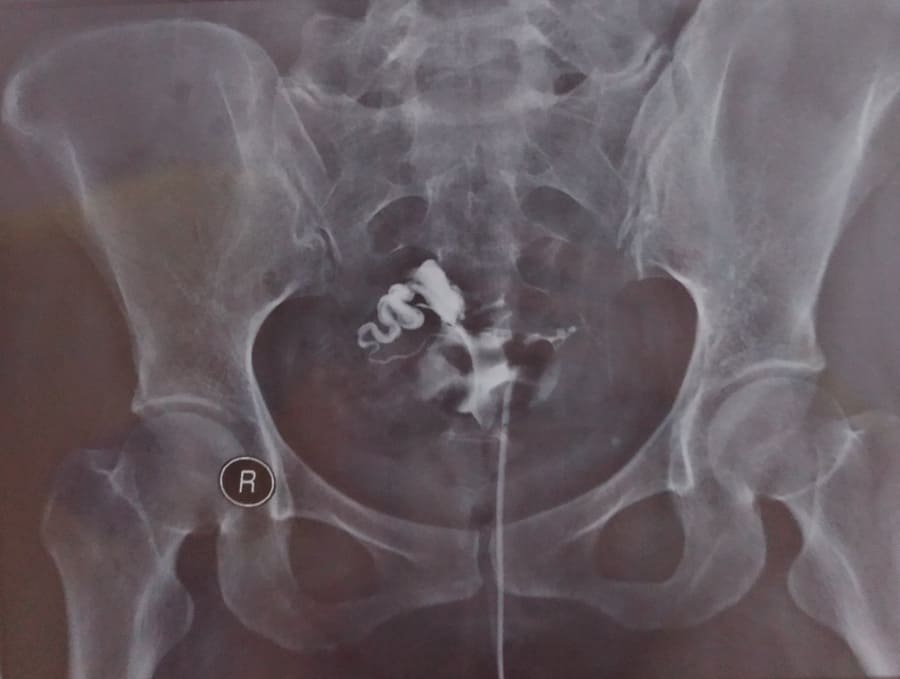

Buat yang belum tahu, HSG (Hysterosalpingography) adalah tes yang menggunakan x-ray/rontgen untuk melihat apakah ada sumbatan dan letak saluran telur atau tuba fallopi/fallopian tubes. Melalui tes ini juga dapat dideteksi kelainan ukuran atau bentuk rahim. Tes ini dilakukan oleh dokter radiologi (bukan dokter SpOG). Prinsipnya cairan kontras yang mengandung iodin dimasukkan memakai kateter ke dalam rahim melalui vagina. Cairan kontras ini akan memenuhi rahim dan saluran telur, kemudian dokter akan mengambil beberapa foto rontgen. Hasil tes HSG berupa saluran telur tidak tersumbat (Tuba Paten) dan saluran telur tersumbat (Tuba Non Paten).

Setelah tes HSG kelar, saya memakai kembali celana dalam plus pembalut. Dokter memberikan resep obat antibiotik anti infeksi, Amoxicillin yang diminum 3x sehari. Harganya adalah Rp 15.400. Setelah menunggu sekitar 1 – 1.5 jam, hasil HSG jadi juga. Tertulis pada kertas:

Uterus : ukuran normal

Kesan :

– Tuba kanan Patent

– Tuba kiri non Patent

Tuba kiri saya tersumbat. Cukup kecewa

tapi juga bersyukur bukan dua-duanya yang tersumbat. Berapa hari sebelum

tes udah parno. Jangan-jangan selama ini tidak hamil karena

masalahnya di aku? Jangan-jangan kedua saluran telurku tersumbat? Ternyata cuma satu dan masih ada harapan walaupun setengah. Positifnya juga, beberapa artikel bilang

setelah tes HSG peluang hamil menjadi lebih besar karena saluran yang

tersumbat ringan bisa jadi plong. Yah semoga saja. Amin.